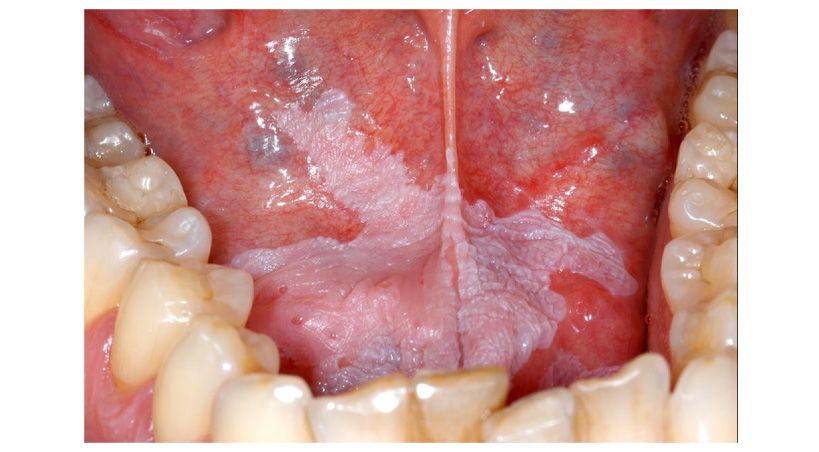

Explicó que la lengua, el paladar, el piso de la boca y maxilares se enferman de igual forma que lo hace la piel, el corazón, el estómago, pero no despiertan interés en los ciudadanos pese a que pueden llegar a ser graves como cáncer bucal.

El experto de la UNAM refirió que la cavidad bucal tiene una gran cantidad de bacterias y hongos que son necesarias para el ser humano, siempre y cuando se mantengan en equilibrio.

Advirtió que es elevada la prevalencia de estos padecimientos, pues se considera que el ciento por ciento de los portadores de placas postizas, esto es la mayoría de los adultos de 60 años y más, padecerá por lo menos, una enfermedad micótica.